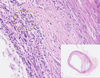

Atherosclerosis of the Artery

Adventitia

Atheroma

Clefts after washing up Cholesterol Crystals

Granular Deposits of Calcium

Intima

Lipophages

Lumen and Fibrous Cap

Lymphocytes

Media

Necrotic Detritus

New Blood Vessels